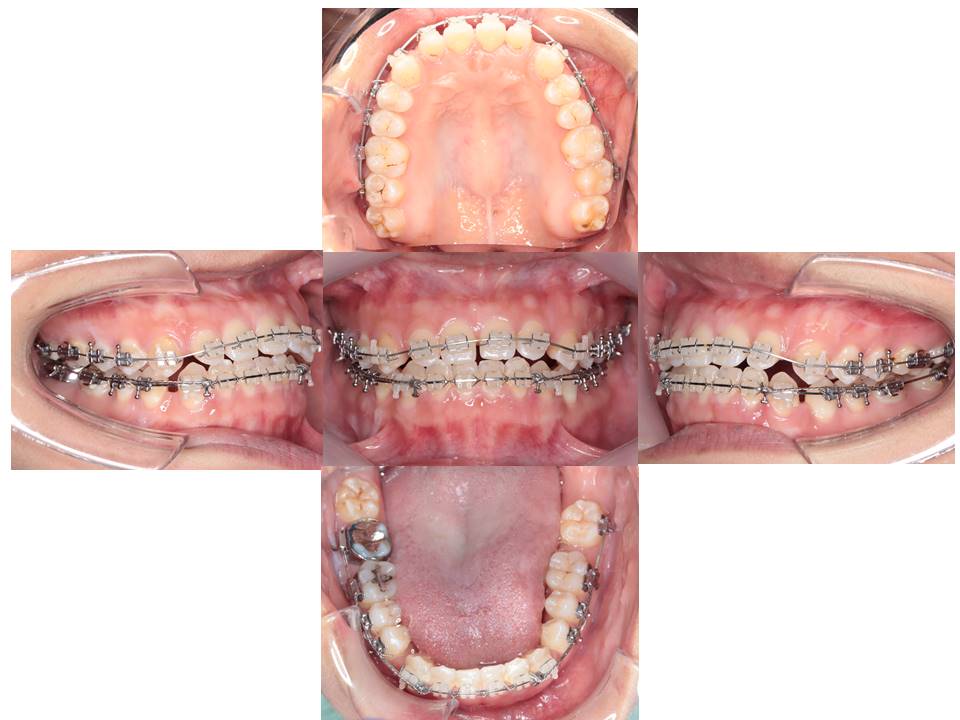

症例の概要

主訴:歯と歯の間の隙間が気になる。

診断名:空隙歯列、開咬、下顎前突

治療経過

上あごと下あごの歯を並べています。

最後の微調整を行っています

治療結果

下の前歯のガタガタは改善され、口元が後退した。